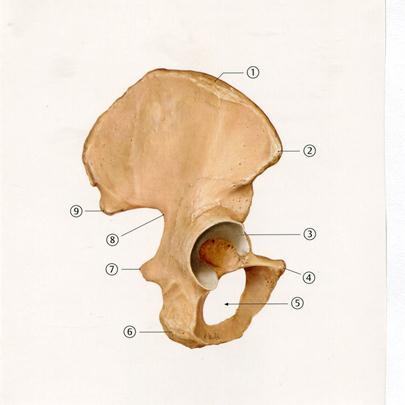

44. Төменде көрсетілген суреттегі белгіленген № 4 анатомиялық құрылымды атаңыз.

A. Алдыңғы жоғарғы қылқан

+B. Алдыңғы төменгі қылқан

D. Үлкен ұршық

E. Шонданай төмпегі

54. Төменде көрсетілген суреттегі №7 белгіленген анатомиялық құрылымды атаңыз.

А. Жапқыш тесік

В. Үлкен шонданай тілігі

С. Ұршық шұңқыры

+D. Шонданай қылқаны

Е. Шонданай төмпесі